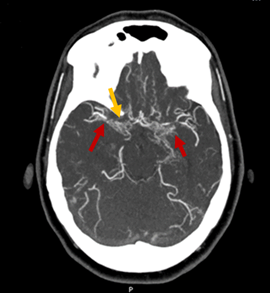

Figure 1 On coronal section CT angiography, bilaterally hypertrophied perforating arteries with a characteristic "smoke cloud" appearance, known as "Moyamoya vessels" are indicated by red arrows.

Despite the unclear CVD, the patient remained asymptomatic until September 2019 when she was admitted for left hemiparesis with dysarthria and conjugate deviation of gaze to the right. The computed tomography (CT) angiography showed a recent right parietal ischemic infarction, occlusion of the terminal portion of the right ICA and the M1 segment of the right middle cerebral artery, and marked stenosis of the terminal portion of the left ICA, the left M1 portion, and the A1 segments of the anterior cerebral arteries, with marked collateral circulation from the lenticulostriate and thalamus-perforating arteries with occlusion of the terminal portion of the ICA, demonstrating the moyamoya pattern (Figure 1 & 2). Progressive neurological deterioration culminated in the patient's death.